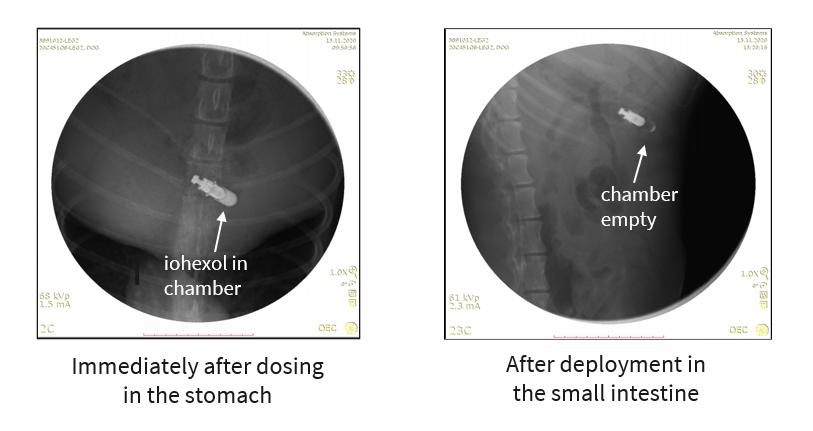

In 2022, we conducted a preclinical study to evaluate the performance and assess the autonomous trigger function of the BioJet device in a canine model, which was presented as a poster at the Parenteral Drug Association Universe of Pre-Filled Syringes and Injection Devices Conference in October 2022. The study was a single-dose study evaluating safety and tolerability of the device in addition to the ability of the device to autonomously actuate in the small intestine. We evaluated device function by loading BioJet devices with a contrast agent (iohexal) and sequentially imaged post-administration as the device transited through the body to show device deployment time and location in the intestine.

This study demonstrated that the BioJet device can reliably deploy in the small intestine, which supports oral administration of the device. The images below are taken from the study and show the contrast agent inside the capsule in the stomach and after deployment in the small intestine.

img189307841_6.jpg